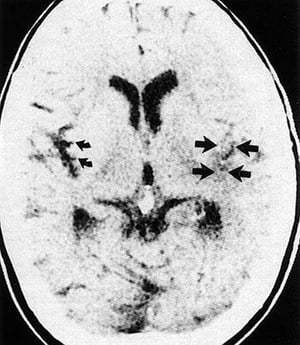

Hypoxische ischämische Hirnschädigung und Hirnödem

Dieses Bild zeigt ein nicht kontrastverstärktes CT bei einem Patienten mit hypoxischer Hirnschädigung und Hirnödem. Man beachte den Verlust der Differenzierung zwischen grauer und weißer Substanz (Kreis), die hypoxisch-ischämische Schädigung der Basalganglien (Pfeile) und die Auslöschung der Sulci.

© 2017 Elliot K. Fishman, MD.